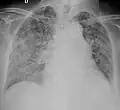

Chest X ray showing miliary tuberculosis

Miliary tuberculosis is a form of tuberculosis that is characterized by a wide dissemination into the human body and by the tiny size of the lesions (1–5 mm). Its name comes from a distinctive pattern seen on a chest radiograph of many tiny spots distributed throughout the lung fields with the appearance similar to millet seeds—thus the term "miliary" tuberculosis. Miliary TB may infect any number of organs, including the lungs, liver, and spleen.[2]